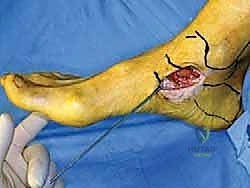

الخطوة الأولى: التخدير والتحضير

يتم إجراء العملية غالبًا تحت التخدير النصفي (Spinal Anesthesia) مع تخدير موضعي للأعصاب الطرفية (Nerve Block) لضمان عدم شعور المريض بأي ألم بعد العملية مباشرة. يتم تعقيم القدم وتجهيزها، واستخدام عاصبة دموية (Tourniquet) لتقليل النزيف وضمان رؤية واضحة للجراح.

الخطوة الثانية: تنظير المفصل التشخيصي والعلاجي (Arthroscopy)

قبل فتح الجانب الإنسي، يقوم الدكتور هطيف بإدخال كاميرا دقيقة (منظار 4K) من خلال ثقوب صغيرة جداً في مقدمة الكاحل. هذه الخطوة حاسمة لتنظيف المفصل من أي أنسجة ملتهبة، وإزالة أي شظايا عظمية أو غضروفية حرة، ومعالجة أي تقرحات في سطح عظمة الكاحل ناتجة عن عدم الاستقرار.

الخطوة الثالثة: الشق الجراحي والوصول الآمن

يتم عمل شق جراحي دقيق ومدروس على الجانب الداخلي للكاحل، خلف وتحت الكعب الإنسي. يستخدم الدكتور هطيف تقنيات تشريحية دقيقة لحماية الهياكل الحيوية المحيطة، وخاصة العصب الصافن (Saphenous Nerve) والوريد المرافق له، لتجنب أي تنميل أو ألم عصبي مزمن بعد الجراحة.